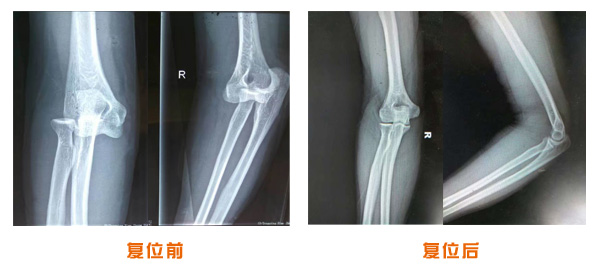

復位前后對比

肘關節脫位骨折治療前后對比